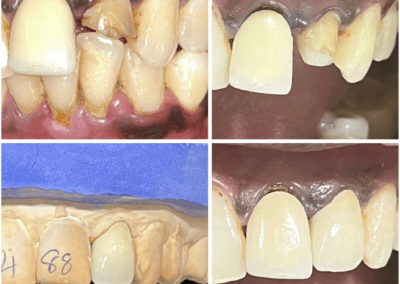

Clinical and Other Media

Candidates with clinical portfolios are expected to provide 10 before and after photographic examples of their clinical work. The most common examples of clinical portfolio work are dental appliances and maxillofacial prosthetics.

Required Clinical Portfolio Examples:

- Before and after photos, on patient are preferred (Authorization for Release of Health Information Form PDF must be collected but is not submitted)

- Photos of a dental appliance, maxillofacial prosthetic device alone without the patient